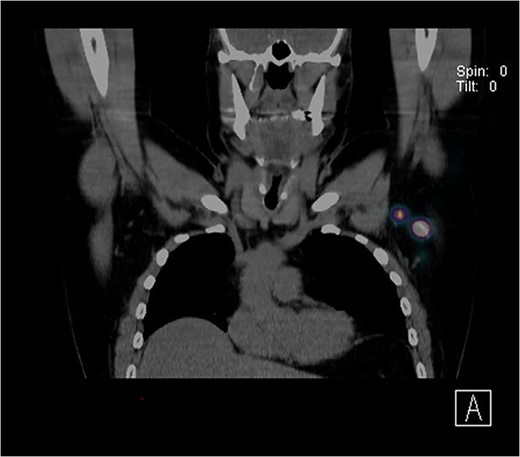

Further wide local excision was performed with margins of 2 cm to deep fascia and keystone flap reconstruction. SLN biopsy was carried out, with dual localization of SLN with Patent Blue V and radio nucleoid tracer. The preop CT single-photon-emission computed tomography (SPECT) imaging showed a focus of tracer activity in two SLNs in the left axilla (Fig. 2). The two lymph nodes were harvested with standard technique.